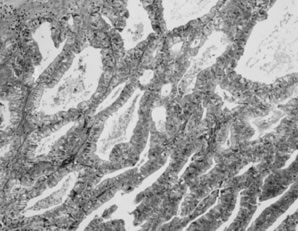

Epithelial implants are papillary and resemble the ovarian APST5,8 (Fig. 2). Mild atypia is often present, and occasionally atypia may be marked. Mitoses are usually absent. Calcification, usually in the form of psammoma bodies, is common and may be extensive.

Fig. 2. Noninvasive peritoneal implant. A papillary proliferation resembling the ovarian atypical proliferative serous tumor is present on the peritoneal surface and does not invade underlying tissue.